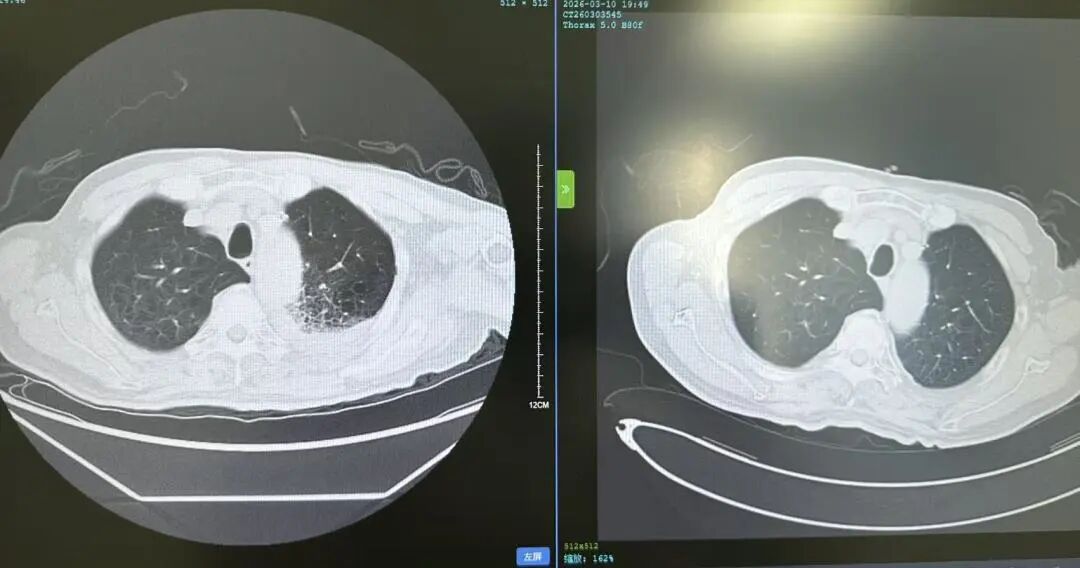

花鸟相伴本是生活雅趣,但鸟类羽毛碎屑、排泄物及粉尘中潜藏的有害物质,却可能悄然成为肺部健康的“隐形杀手”。这类疾病起病隐匿、症状不典型,极易被误诊或漏诊,严重时甚至可迅速进展为重症肺炎、呼吸衰竭,危及生命。近日,葫芦岛市第二人民医院呼吸与危重症医学科连续收治多例与接触鸟类密切相关的肺部疾病患者,为广大“养鸟一族”敲响警钟。 病例一:久咳不愈竟致呼吸衰竭 真凶竟是“养鸟过敏” 50岁的刘先生咳嗽、咳痰、气短两个月,严重时彻夜难眠,辗转求医无果,入院时已确诊I型呼吸衰竭。肺部影像学检查显示,双肺广泛存在磨玻璃影,局部已呈现“白肺”表现。此时,鉴别是感染性还是非感染性因素,成为诊断的关键。 ↑氧分压<60mmHg、二氧化碳氧分压正常、呼吸频率异常,呼吸衰竭 ↑相关检验项目正常,排除感染性因素 宋刚主任细致追问病史,发现其长期接触鸟类,结合支气管镜检查排除常见感染,最终明确诊断为外源性过敏性肺泡炎(过敏性肺炎),合并急性喘息性支气管炎。病因正是吸入鸟类羽毛及排泄物中的特异性蛋白过敏原,导致肺部过敏性炎症损伤。在脱离过敏原、接受经鼻高流量等规范治疗后,刘先生症状迅速缓解,顺利康复出院。 ↑左侧为治疗后肺部影像,右侧为治疗前肺部影像,肺炎明显减轻 病例二:高龄重症合并多重基础病 幕后黑手竟是鹦鹉热衣原体 86岁的杨大爷持续高热3天,体温达39℃,入院时已出现严重呼吸衰竭。更棘手的是,患者有20年再生障碍性贫血病史,白细胞、血小板极低,属典型免疫抑制,极易感染罕见病原菌。因血小板过低,行支气管镜检查出血风险极高。科室另辟蹊径,采用痰液NGS检测,精准锁定了致病元凶——鹦鹉热衣原体,这是一种经鸟类传播的非典型病原菌。 ↑鹦鹉热衣原体检测结果 ↑患者再生障碍性贫血,白细胞、血小板极低 诊断明确,治疗却面临两难:患者合并下肢静脉血栓,本应进行抗凝治疗,却因血小板严重低下受限。医疗团队综合研判、分层施策,严密监测血氧及肺栓塞风险,同步控制感染,并多次输注血小板、白蛋白及免疫球蛋白加强支持治疗。经综合救治,杨大爷病情好转,顺利出院。 ↑左侧为治疗前影像,右侧为治疗后影像,感染明显好转 病例三:体检发现肺部团块影 不是肺癌是真菌 患者养鸟多年,体检时发现右下肺团块状阴影,家属一度担心是肿瘤。但宋刚主任对比前年肺部影像,凭借丰富经验判断:恶性肿瘤在一年内长成如此大的团块相对少见,且病灶周围有典型晕征,高度怀疑是隐球菌肺炎——这是一种真菌性感染病,致病菌常寄生于鸟类粪便中。随后通过隐球菌荚膜多糖抗原检测,快速明确隐球菌肺炎诊断,规范抗真菌治疗后,病灶逐步缩小,病情控制稳定。 ↑隐球菌肺炎疗程较长,左侧为治疗后1个月的肺部影像,右侧为治疗前肺部影像,可见左侧晕征较右侧减轻 专家提醒:养鸟有风险 呼吸不适须警惕 宋刚主任表示,日常养鸟需做好防护: ☑ 注意环境卫生,保持通风干燥,控制粉尘; ☑ 定期清洁鸟笼与排泄物,清理时佩戴口罩、手套,避免直接接触; ☑ 老人、免疫低下、基础病较多者更需格外警惕。若出现长期咳嗽、气短、发热等症状,且有鸟类接触史,务必及时到专业呼吸科就诊,避免误诊漏诊。 我院呼吸与危重症医学科作为市级重点专科,致力于各类重症肺炎、呼吸衰竭、慢性气道疾病、哮喘等疾病的鉴别及规范化治疗,复杂疑难重症诊疗能力突出。同时携手中国医科大学附属第一医院,顶尖呼吸科专家每月定期来院出诊,让滨城百姓在家门口就能享受到省级优质医疗服务,为群众呼吸健康筑牢坚实屏障。 人民医院 人民名医 宋刚 主任医师 ·葫芦岛市第二人民医院呼吸与危重症医学科主任 ·辽宁省生命科学学会东北呼吸与危重症医学(PCCM)分会辽宁省基层委员会副主任委员 ·辽宁省细胞生物学学会放射粒子治疗专业委员会理事 ·辽宁省抗击新冠肺炎疫情先进个人 ·辽宁省预防医学会第一届吸烟相关疾病防治专业委员会委员 ·葫芦岛市劳动鉴定委员会专家库成员 ·葫芦岛市医学会呼吸内科学分会第三届委员会副主任委员 专业特色:擅长呼吸系统疑难及急危重患者的救治,如急慢性支气管炎、支气管哮喘、慢性阻塞性肺疾病、肺炎、肺栓塞、肺癌、间质性肺疾病、睡眠呼吸暂停综合征等,尤其擅长有创无创机械通气、支气管镜下相关检查及治疗(TBNA、气道支架置入术、球囊扩张等)、全肺灌洗术等领先技术,发表国家级期刊多篇。 出诊时间:每周二、周四全天 出诊地点:门诊二楼东侧35诊室 咨询热线:0429-8010115